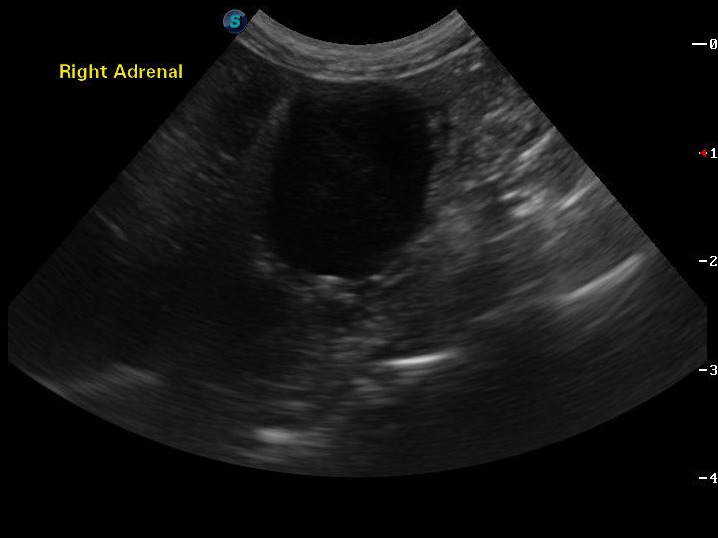

CT

Abdominal CT of Adrenal mass.

Ultrasound

Abdominal Ultrasound of Adrenal Mass.